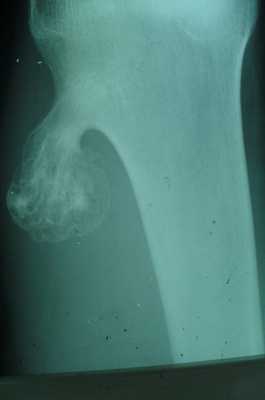

Гигантоклеточная опухоль

(остеобластокластома)

- состоит из клеток 2 типов- многоядерных гигантских и мелких одноядерных,

- поражаются люди в возрасте от 20 до 40 лет,

- локализация бедренная кость - дистальный конец, проксимальный конец б/берцовой кости, дистальный конец лучевой кости. Из плоских костей - тазовые кости и лопатка, очень редкая локализация в позвонках,

- одиночность и изолированность поражения,

- характерно расположение опухоли в эпиметафизраном отделе, который значительно вздут и деформирован, имеет вид крупнобугристого полушария, булавы,

- опухоль доходит до суставного хряща и обрывается,

- растет во всех направлениях, но главный рост происходит вдоль длинной оси кости в сторону с/3 диафиза кости,

- поперечник опухоли может увеличивать нормальный диаметр опухоли в 3-5 раз.

- ячеистый тип - опухоль состоит из отдельных камер, отделенных друг от друга полными и неполными перегородками (мыльные пузыри или неправильные соты),

- корковое вещество раздвигается, вздувается изнутри, истончается, надкостничных наслоений нет,

- при больших опухолях корковое вещество рассасывается и опухоль окружена со всех сторон тонкой скорлупой состоящая из стенок поверхностно расположенных ячеек.

- остеолитический тип - полное отсутствие ячеистого или трабекулярного рисунка, дефект кости вполне гомогенен,

- краевой блюдцеобразный дефект,

- корковый слой на пораженном месте рассасывается, а на границе с дефектом корка заострена, не подрыта и не имеет никаких периостальных наслоений,

- контуры дефекта резкие,

- патологические переломы в 12% случаев.